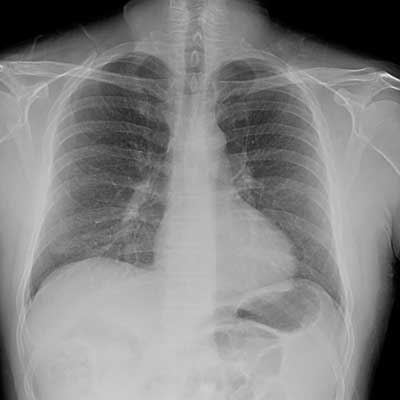

Реакция непереносимости на попугая опасно возможным развитием альвеолита, то есть поражением легких.

При такой реакции на альвеолах образуются уплотнения, которые значительно снижают проходимость воздушного потока и этим самым вызывают самую тяжелую симптоматику болезни.

Аллергия на птиц развивается и появляется точно также — все дело именно в этом белке – антигене, который содержится в большом количестве в слюне птицы. При очистке перьев, когда попугай совершает гигиенические процедуры, мельчайшие частички вещества попадают в окружающий воздух. Человек вдыхает их – те, что покрупнее, задерживаются в носовой полости или трахее, вызывая ринит, а те, что помельче – попадают сразу в легкие, вызывая аллергический альвеолит. Он редко развивается быстро и сразу – вначале обычно появляются различные респираторные проявления патологического процесса.

Может ли быть аллергия на птиц быть опасна для жизни? Одной неприятной особенностью этого заболевания является то, что ухудшение состояния человека происходит достаточно медленно и практически бессимптомно. Аллергия на попугаев считается очень опасной – она влияет непосредственно и сразу на легкие человека. Под воздействием птичьего белка альвеолы значительно уплотняются, что приводит к затруднению, а иногда и потере, дыхания. Кислород не поступает в легкие в достаточном количестве, отчего, особенно во время обострения аллергической реакции, происходит уменьшение их объема – практически в 2-3 раза. Заболевание может развиваться в нескольких формах – все зависит и от длительности и частоты контакта человека с антигеном, и от особенностей его иммунной системы:

Аллергигический альвеолит — это заболевание, которое вызывается аллергической болезнью легких. Данное название произошло от того, что аллергическая реакция возникает не на слизистых оболочках, а конкретно в легких на их альвеолах.

Конечно же, аллерген в данном случае должен иметь настолько мелкие частички, чтобы при вдыхании он не мог задерживаться в носу, бронхах или трахеях, а попадал с потоком воздуха напрямую в легкие. Поэтому для того, чтобы определить, есть ли аллергия на попугаев, нужно проверить имеется ли у вашего организма негативная реакция на такой аллерген как птичий белок. И сделать такой анализ лучше перед тем, как завести попугайчика.

- Уплотнения на пораженных участках. Пораженные участки альвеол оказываются в итоге без воздуха. Ребенку становится тяжело вдыхать и выдыхать полной грудью.

- Происходит обструкция в бронхах и легких.

- Емкость легких уменьшается в три, а то и в четыре раза.

- Наступает нарушение циркуляции воздуха в организме.

Возникает альвеолит при оседании большого количества аллергена в нижних частях дыхательных путей, в результате чего поражаются ткани легких и человек может задохнуться без соответствующей медикаментозной помощи.